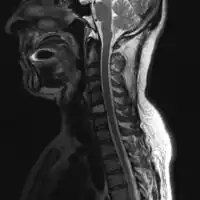

2.a. MRI neck (side view): solitary plasmacytoma C6